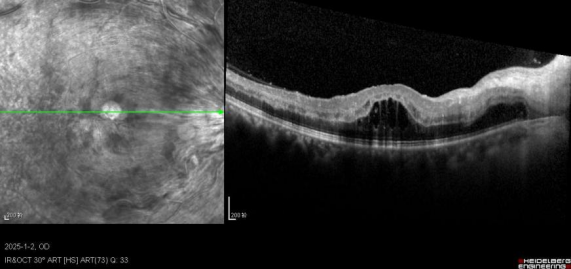

左眼OCT:黄斑区视网膜内强反射物质,黄斑囊样水肿,伴视网膜下液(SRF),CRT 861 μm

根据患者病史、症状、眼部体征及辅助检查,诊断为左眼CRVO、双眼白内障、双眼玻璃体混浊。给予左眼康柏西普玻璃体腔注射治疗,初始采用3+PRN治疗方案(前6针),患者随访病情稳定后,后续调整为治疗-延长(T&E)方案。康柏西普治疗1次后,视力即由0.06提升至0.3,CRT由861 μm显著下降至444 μm。连续3次治疗后,视网膜内强反射物质基本消退,SRF完全吸收,CRT 256 μm。治疗后长期随访20个月结果显示,患者视力与CRT持续改善并保持稳定。左眼视力从治疗前0.06逐步提升,20个月时达到0.6;CRT从治疗前861 μm逐步下降,20个月时稳定在266 μm。

图:左眼进行康柏西普治疗前后的OCT:康柏西普治疗1次后1个月,CRT较基线降低417 μm;连续3次治疗后,视网膜内强反射物质基本消退,SRF完全吸收(CRT 256 μm);第20个月复诊,CRT289 μm,予以第9次治疗(治疗后CRT266 μm)